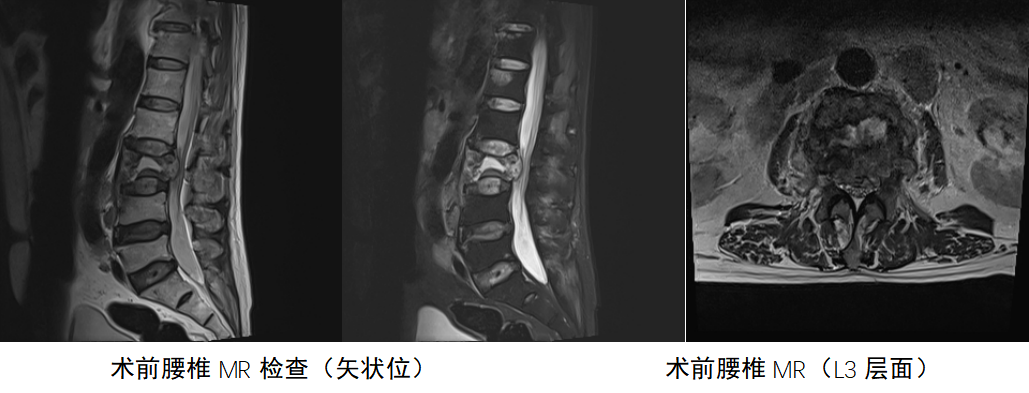

2025年8月 腰椎MR:L3椎体骨折并侵入椎管

腰椎MRI(平扫+增强):L3椎体及左侧椎弓根、椎板见明显异常强化信号影,T1WI呈低信号,T2WI/STIR呈不均匀高信号,硬膜囊受压明显。